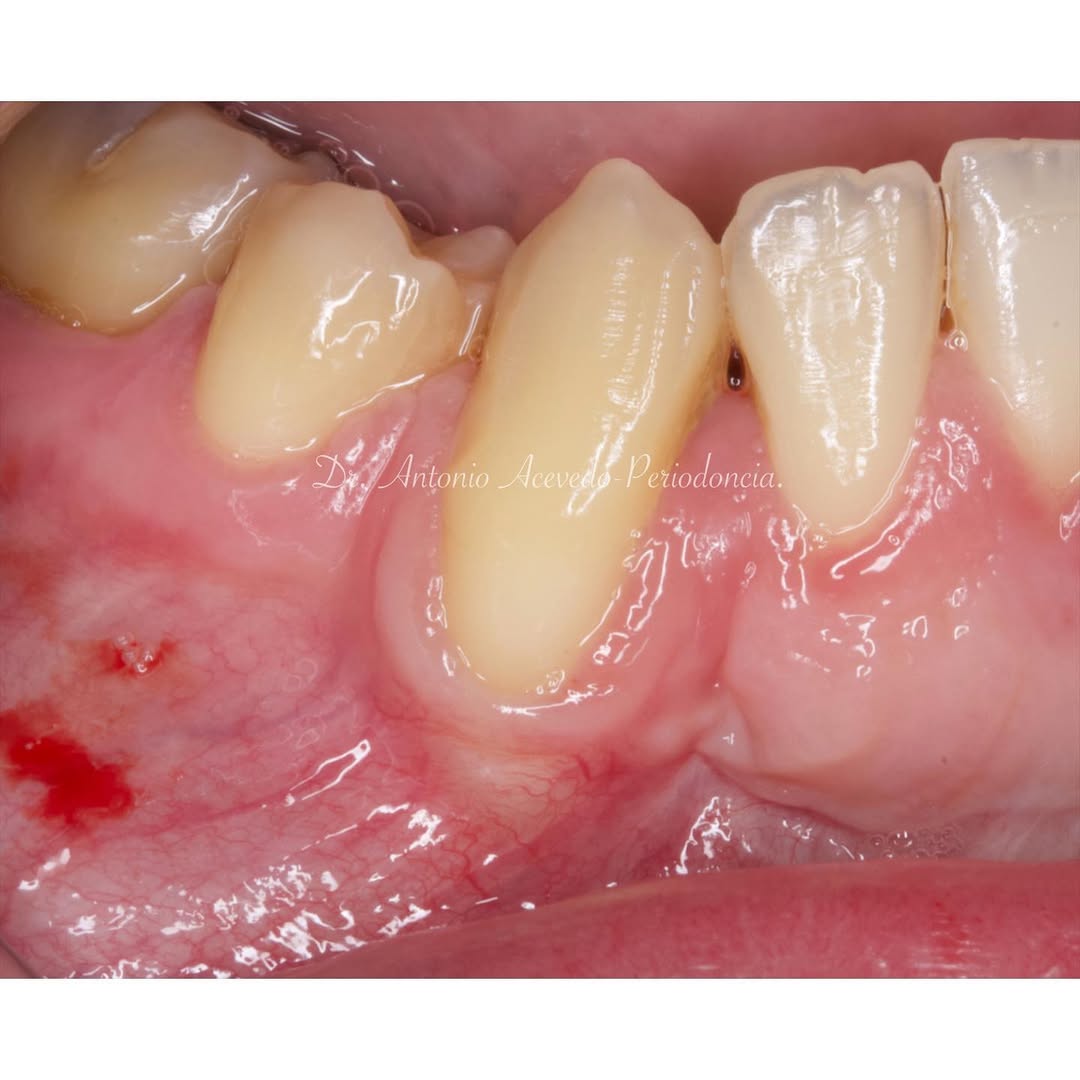

Podrás asistir a la planificación de casos y cirugía de injerto de tejido conectivo. Factores determinantes y elección de la técnica adecuada. Sumérgete en un protocolo predecible y técnicamente correcto para obtener resultados óptimos.